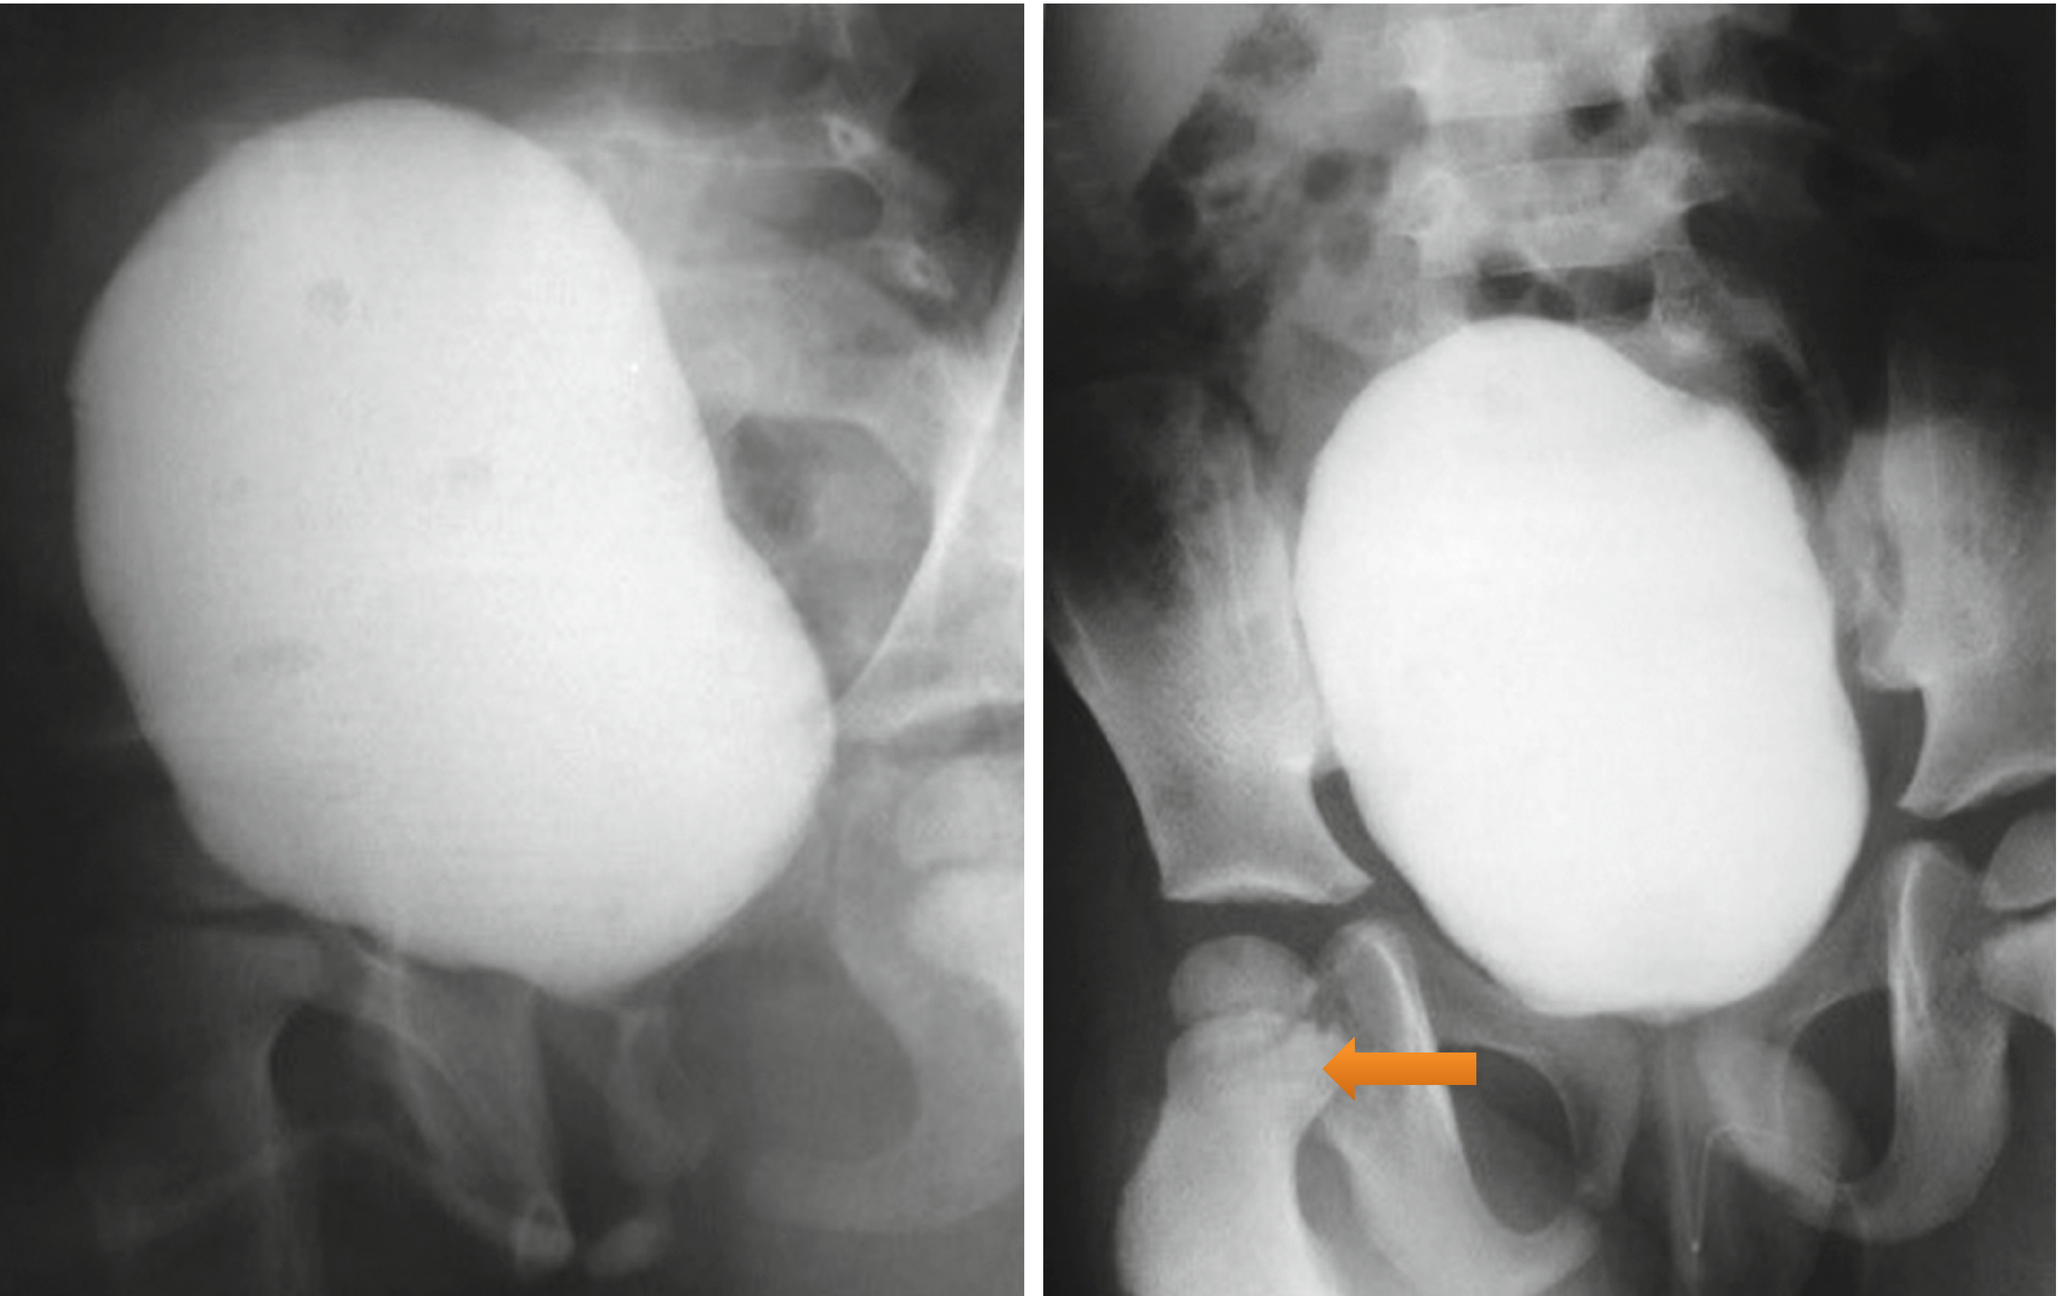

Download Posterior Urethral Valves Radiology PNG. Posterior urethral valve (puv) disorder is an obstructive developmental anomaly in the urethra and genitourinary system of male newborns. A posterior urethral valve is an abnormal congenital obstructing membrane that is located within problems resulting from the presence of a posterior urethral valve are depicted in the image below.

Membranous tissue in the posterior urethra results in varying degrees of obstruction. Posterior urethral valves consist of a thin membrane of tissue (fig 1) that is the most common cause of lower urinary tract obstruction in male infants, occurring in between 1 in 8000 to 1 in 25 000 live births.1 posterior urethral valves affect both the upper and the lower urinary tract. Puv are also the most common cause of chronic.

The most common cause of lower urinary tract obstruction in male infants is posterior urethral valves.

Posterior urethral valve disorder is an obstructive developmental anomaly in the urethra and genitourinary system of male newborns. Posterior urethral valves (puv) are obstructive membranes that develop in the urethra (tube that drains urine from the bladder), close to the bladder. Posterior urethral valves (puvs) was first described from hugh hampton young in 1919 (1). The left kidney displays normal uptake and excretion of nuclear tracer.